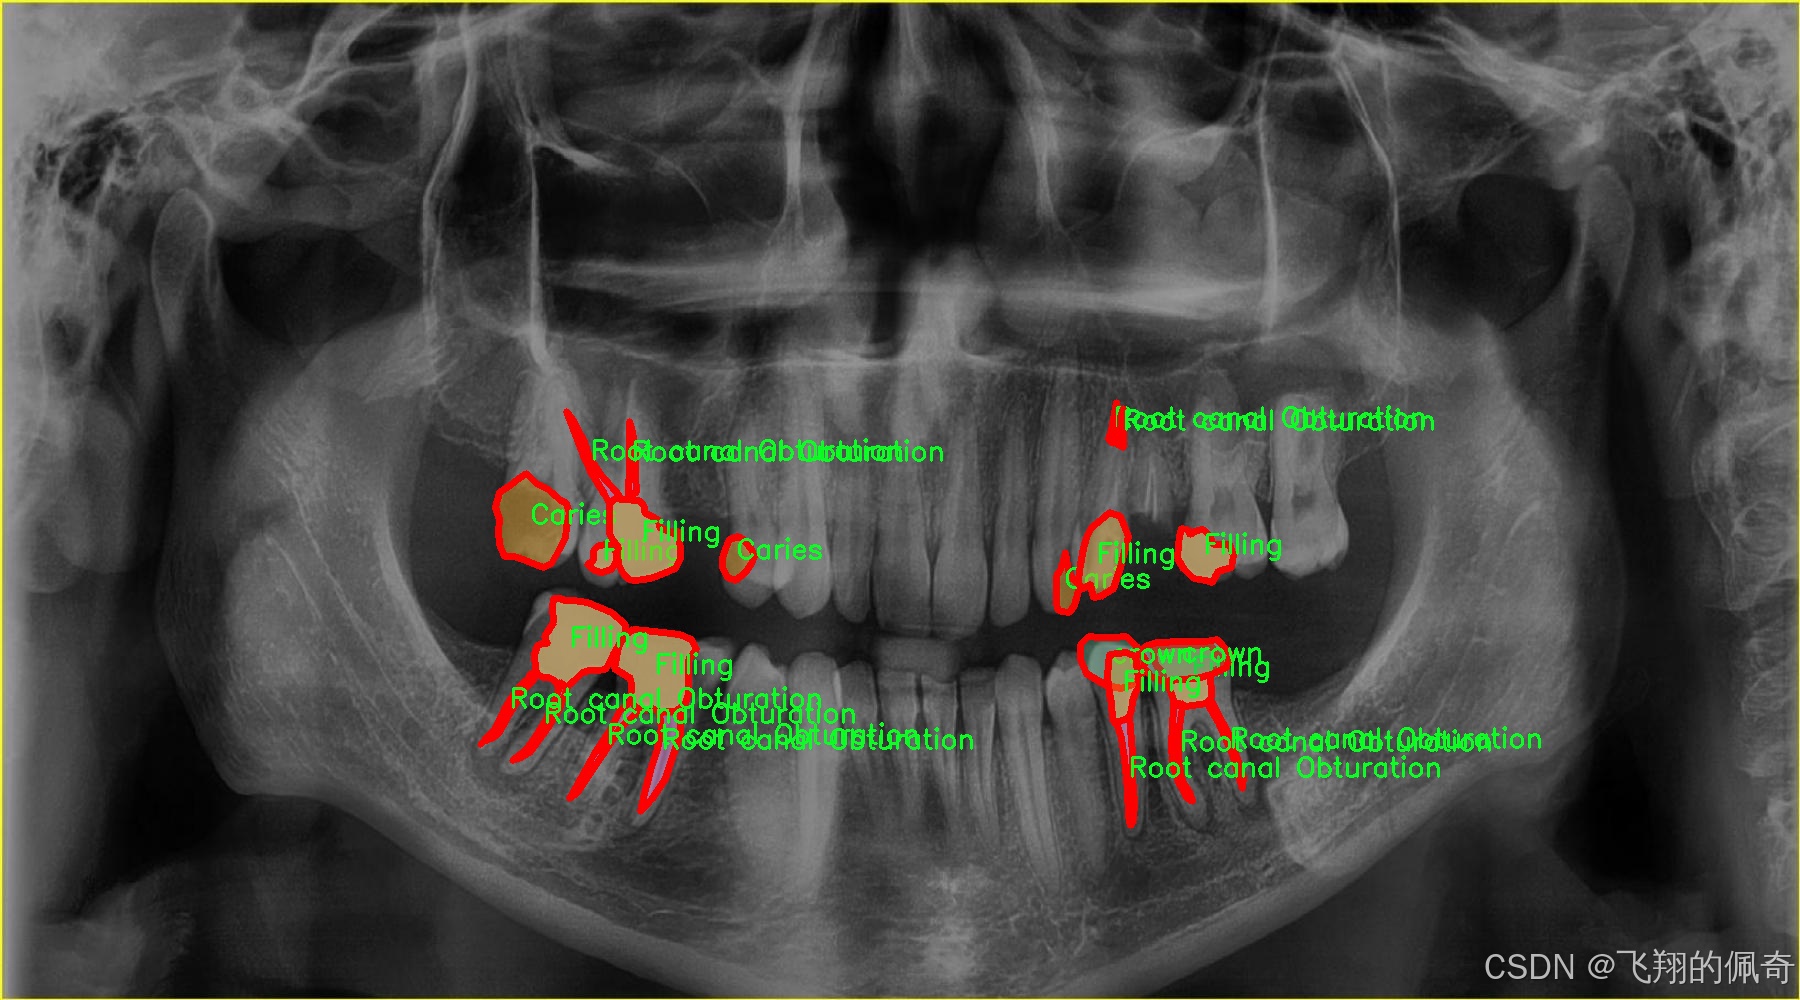

本研究旨在基于改进的YOLOv8模型,构建一个高效的龋齿牙齿病变图像分割系统。我们将利用一个包含5100张图像的龋齿分割数据集,该数据集涵盖了23个类别,包括各种类型的牙齿病变,如龋齿、根管治疗、牙冠、牙桥等。这些类别的多样性为模型的训练提供了丰富的样本,有助于提高模型的泛化能力和准确性。此外,数据集中不同病变的标注信息将为模型的学习提供清晰的目标,促进其在实际应用中的表现。

在现代牙科医学中,龋齿的早期诊断与治疗至关重要,而图像分割技术在这一领域的应用为牙科医生提供了更为精确的工具。为此,我们构建了一个名为“tooth segmentation”的数据集,旨在训练改进版的YOLOv8-seg模型,以实现对牙齿病变图像的高效分割。该数据集专注于八种不同的牙齿病变类型,涵盖了从龋齿到各种修复体的多样性,确保模型能够识别和分割这些关键特征。

“tooth segmentation”数据集包含八个类别,分别为:龋齿(Caries)、牙冠与桥(Crown-Bridge)、填充物(Filling)、植牙(Implant)、后螺钉(Post-screw)、根管填充(Root canal Obturation)、牙冠(crown)以及再植体(implant)。这些类别不仅代表了牙齿的不同病变状态,还涵盖了牙科治疗中常见的修复和重建过程。这种多样性使得数据集在训练过程中能够有效地提高模型的泛化能力,帮助其在实际应用中更好地适应不同的病例。